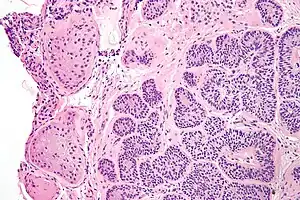

| Micrograph of a Sertoli cell nodule. H&E stain. | |

Sertoli cell nodules are unencapsulated nodules that consist of:[1][2][3]

- cells arranged in well-formed tubules (that vaguely resemble immature Sertoli cells), with

- bland hyperchromatic oval/round nuclei that are stratified, and

- may contain eosinophilic (hyaline) blob in lumen (centre).